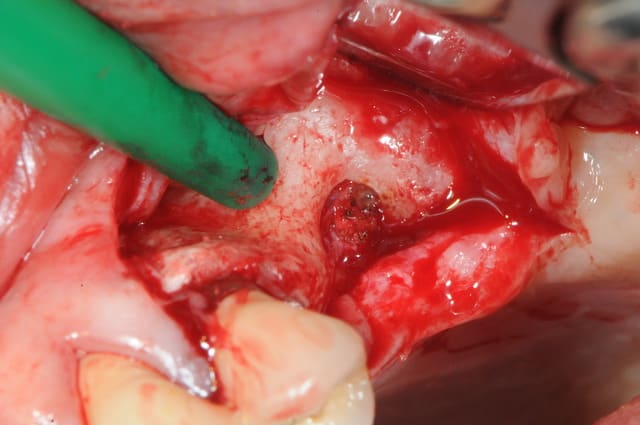

je dois pratiquer un rehaussement de plancher sinusien par volet latéral et je ne sais comment gérer le décollement de la membrane de Schneider au niveau de la communication bucco sinusale

Dès le départ, je m'inquiète au niveau du décollement du lambeau sur la CBS, on risque de déchirer à ce moment là

je joins quelques captures pour vous faire une idée

c'est une idée mais alors comment décoller le lambeau au niveau de la CBS? en épaisseur partielle?

à moins de d'inciser en forme de cercle autour de la CBS

puis de décoller en épaisseur totale autour, puis de rentrer la "chaussette" après avoir agrandi la fenêtre?